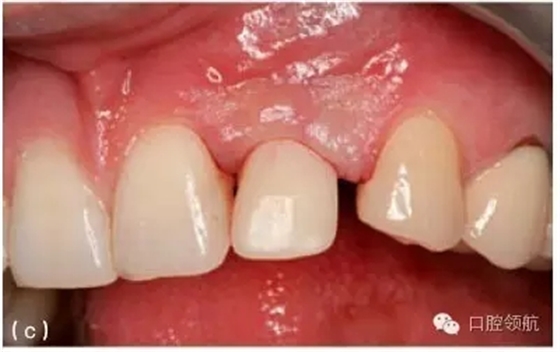

種植體周圍有一個淺的組織袖口,但這個袖口可能位于鄰近牙或種植體的根方。當(dāng)種植體植入時,牙槽嵴已經(jīng)發(fā)生垂直吸收,就會出現(xiàn)這種情況。當(dāng)種植體植入這些未行位點恢復(fù)的區(qū)域時,種植體跟鄰牙間的牙齦不在同一水平,這將造成不平整的牙齦形態(tài)。如果修復(fù)體在美學(xué)區(qū)域內(nèi),使用齦色瓷(或復(fù)合材料)可以部分遮蓋牙齦高度差異(圖9.24a,b)。另外,當(dāng)一個長的臨床牙冠可以被患者的嘴唇遮蓋時,這種方案也是可取的。因而,在制訂治療計劃的時期,就要考慮到是否存在不一致的骨水平。為了克服這些不一致的情況,獲得滿意的修復(fù)效果,使用CT檢查及外科模板,有利于評估預(yù)期修復(fù)體與缺失軟硬組織之間的

關(guān)系。如果這些不規(guī)則的差異,在美學(xué)方面不能讓患者滿意,醫(yī)生在診斷和進行外科手術(shù)之前,必須充分評估及討論缺失組織的再生潛力。

圖9.24 (a) 由于種植體植入前,沒有進行充分的位點恢復(fù),最終在修復(fù)體唇面輔以齦色瓷,以彌補軟組織的不足。(b)口內(nèi)全景觀,全口烤瓷熔附金屬修復(fù)體,粘結(jié)固位,注意左側(cè)側(cè)切牙牙齦區(qū)域的齦色瓷。